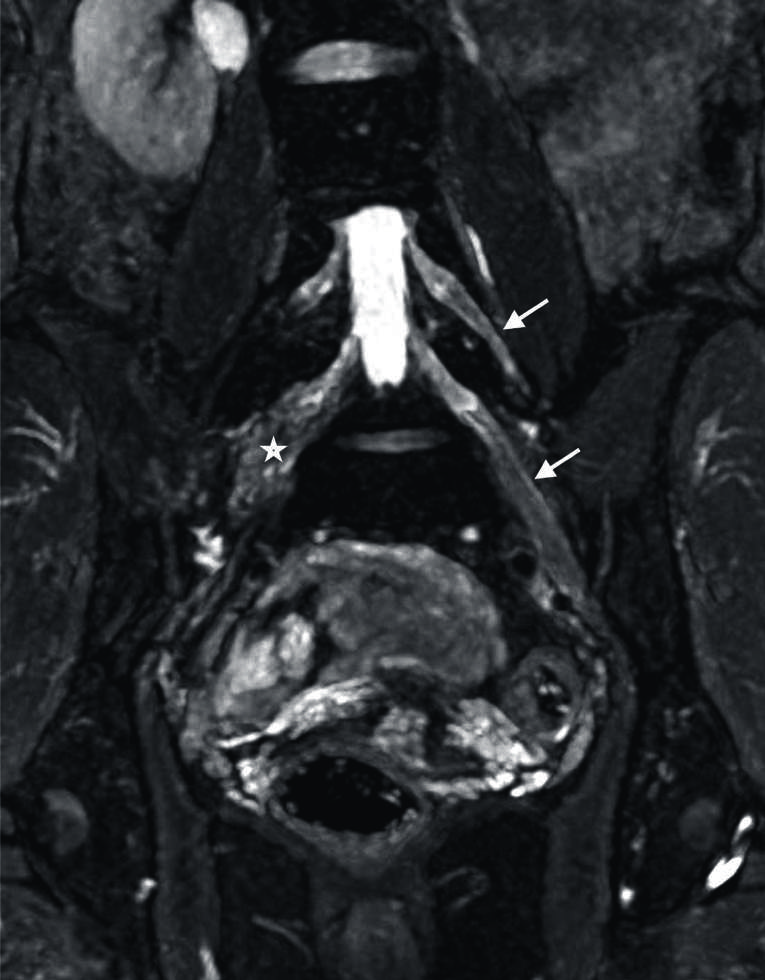

Figura 11

Sindrome de Parsonage Turner en un joven de 18 años.

Secuencia neurográfica IDEAL water en ponderación T2, en la que se observa engrosamiento e hiperseñal de los troncos y divisiones del plexo braquial izquierdo (flechas).

El sindrome de Parsonage Turner, es una plexitis autoimmune de etiología desconocida que afecta a pacientes de edad media. La características clinicas son el dolor, seguido por denervación rápida de los músculos del hombro y miembro superior afectados (52). En NRM, se observa la hipertrofia difusa e hiperseñal en ponderación T2 de las ramas del plexo braquial. Cabe resaltar, que suele observarse afectación de otros ramos menores como nervio torácico largo, supraescapular, subescapular. Por otra parte, en el 30 % de los casos suele ser bilateral, aunque clínicamente los sintomas persistan de un solo lado. Este dato le da mayor importancia al estudio neurográfico porque al aportar el dato de bilateralidad ayuda a indicar la rehabilitación de ambos miembros aunque el paciente no perciba sintomas en uno de ellos (53). (Fig. 11).